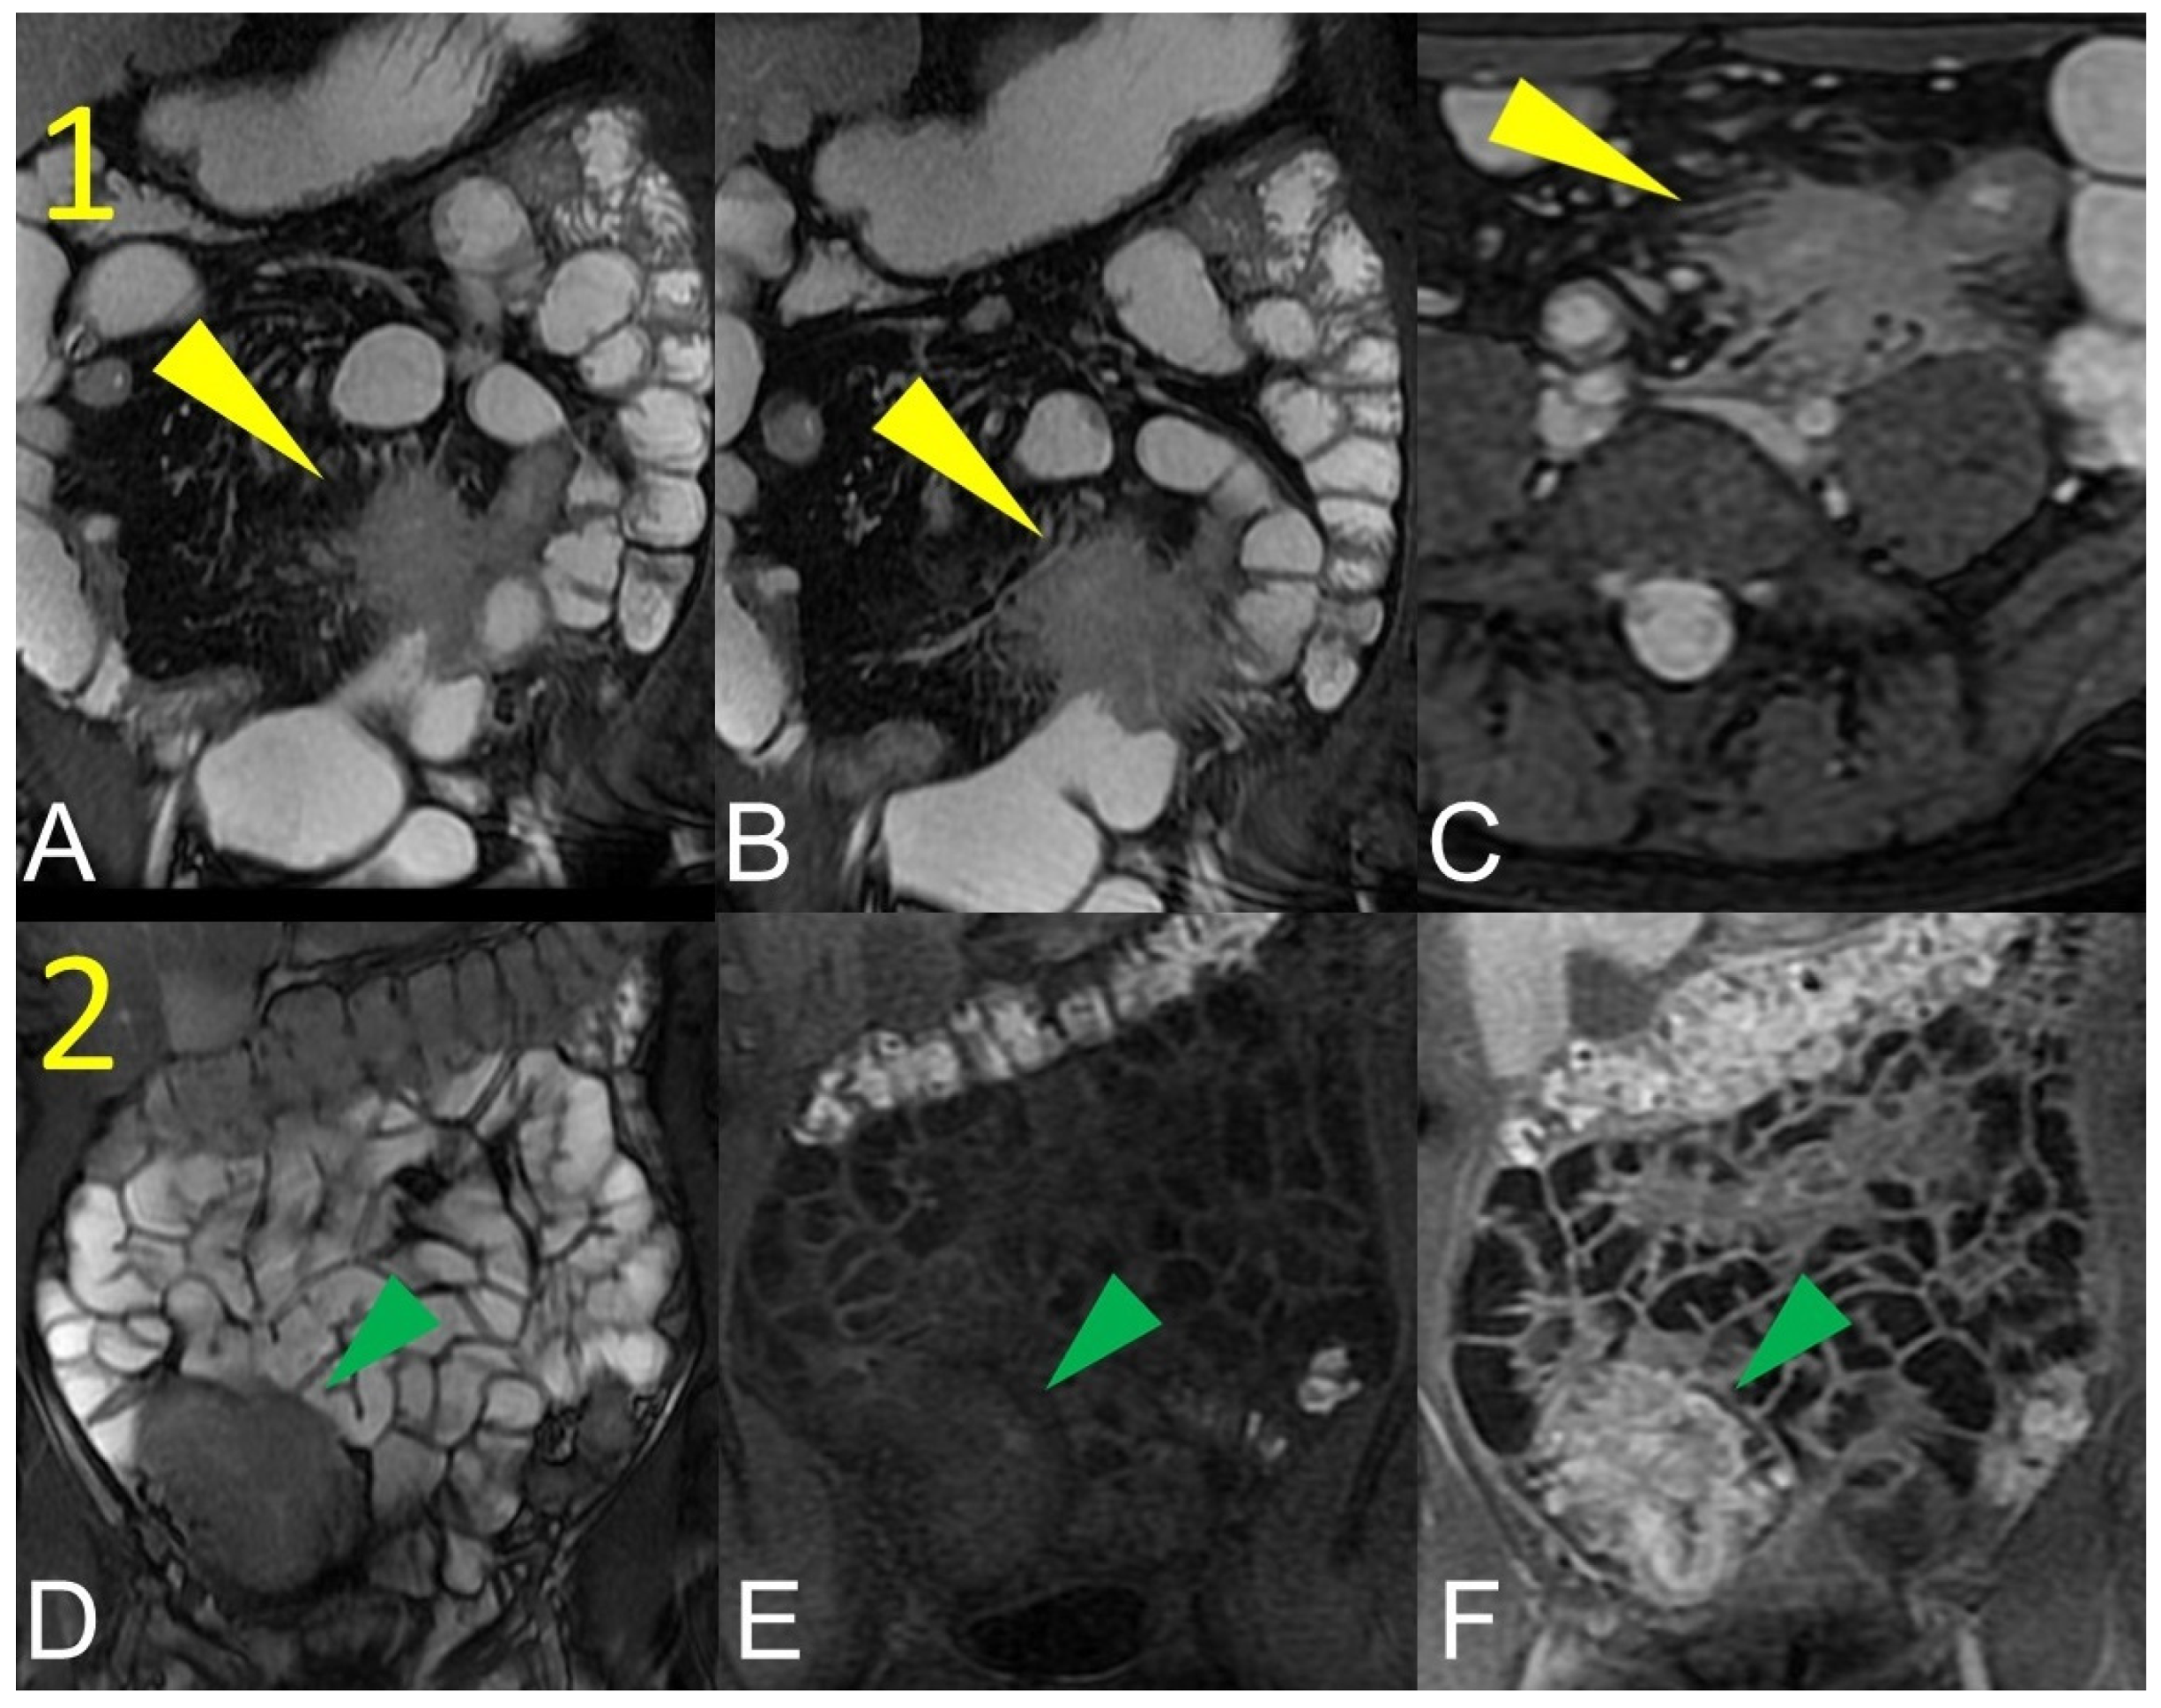

Figure 12.

Inflammatory conglomerate represents a climbing mesenteric fat involvement in the context of penetrating disease and mesenteric inflammation. The components of the fistulas within the mass can be difficult to detect because it often coexists with phenomena of retraction that are expressed on the intestinal loops nearby or on the ureters. Small inflammatory conglomerate in the context of the mesentery adherent to a segment of the pathological small intestine, with active disease (yellow arrowheads in (A,C): coronal (A) and axial (C) contrast-enhanced fat-suppressed T1-weighted image and in (B,E) (coronal fast imaging employing steady-state acquisition; FIESTA image) and (D) (coronal T2-weighted MRE image)).

Figure 13.

Two different patients with, respectively, an inflammatory conglomerate (Patient 1) of medium size (yellow arrowheads in (A–C)) and of large size (green arrowheads in (D–F)) (Patient 2). Coronal (A,B) and axial (C) fast imaging employing steady-state acquisition (FIESTA) image. Coronal FIESTA image (D) and coronal without (E) and with (F) contrast-enhanced fat-suppressed T1-weighted image. Notably intense contrast enhancement in (F) image underlines the significant state of inflammation of the disease in the active and complicated phase.